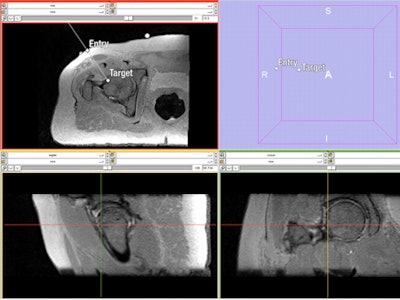

![]() |

| Needle path planning to the femoral head-neck junction with 3D sampling perfection with application optimized contrast using different flip angle evolutions (SPACE) MRI sequence. Axial reformation is shown on the top left, while a 3D map is on the top right. A sagittal reformation is presented on the bottom left, and a coronal reformation is on the bottom right. |